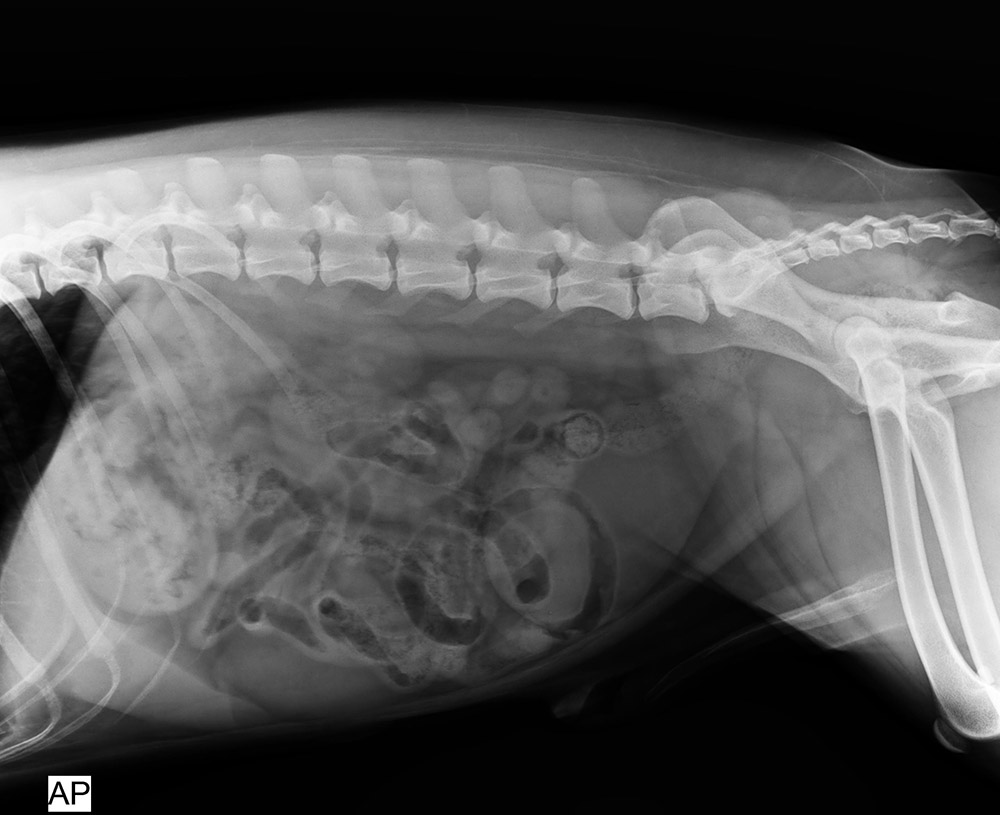

北京愛瑞可動物醫(yī)院